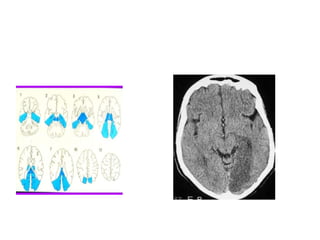

• Anterior cerebral artery

• The anterior cerebral artery (ACA) branches off

the internal carotid artery and supplies the

anterior medial portions of the frontal and

parietal lobes.

• Classic signs of an ACA stroke are contralateral leg

weakness and sensory loss. Keep in mind that

behavioral abnormalities and incontinence also

may occur.

Effects of a complete MCA stroke

• The hallmarks of an MCA stroke are the focus of most

public-awareness messages and prehospital stroke

assessment tools—facial asymmetry, arm weakness, and

speech deficits. Complete MCA strokes typically cause:

• hemiplegia (paralysis) of the contralateral side, affecting

the lower part of the face, arm, and hand while largely

sparing the leg

• contralateral (opposite-side) sensory loss in the same areas

• contralateral homonymous hemianopia—visual-field

deficits affecting the same half of the visual field in both

eyes.